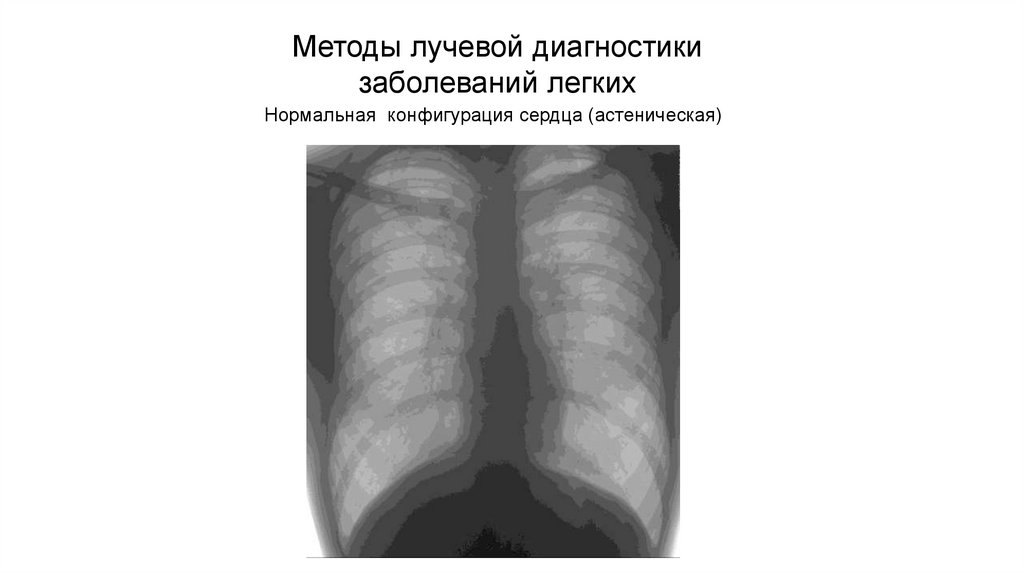

Рентгенологические изображения и синдромы патологии легких

Раздел: Кадры-подсказки